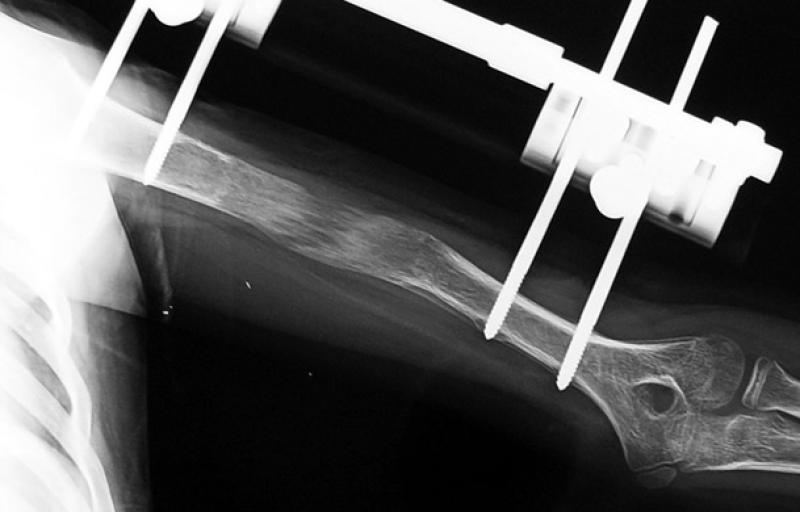

For length differences of more than 2 cm, surgical intervention is necessary. With lengthening surgery, which is an orthopaedic process, patient’s functional capabilities can be improved for lengthening. For children, the shorter side can be lengthened to equalise limb length and rarely, the growth of longer side can be slowed down.

Lengthening surgery can be performed for adults above 18 years of age and for aesthetic concerns apart from diseases. For people with wrongly mended fractures, diabetes, smokers, or accident victims who have short stature, bone correction with special techniques can be used to equalise limb length. For lengthening due to cosmetic reasons, patients have to go through psychiatric evaluation. With the help of special devices and techniques, lengthening between a quarter millimetres and 1 millimetres is provided. 10 - 15 cm of growth is possible according to reason of short stature, age, and bone structure. Patients have to receive physical treatment after the surgery for development of muscles.

After the lengthening surgery, height growth starts following the end of 7-10 days of recovery period. An average of 5cm of lengthening is provided for legs with 1mm lengthening per day for two months. According to the used technique, the lengthening time for 1cm can change between 1.5-2 months, and 4-6 for 5cm.

When the desired lengthening amount is achieved, the lengthening is stopped in the second stage and 45-90 days are waited for the elongated bone to harden and get stronger. For hand fingers with shape disorders, lengthening occurs at the rate of a quarter millimetres per day. Lengthening surgeries every 4-5 years are performed on children and all sessions are completed by the age of 20 at the latest.